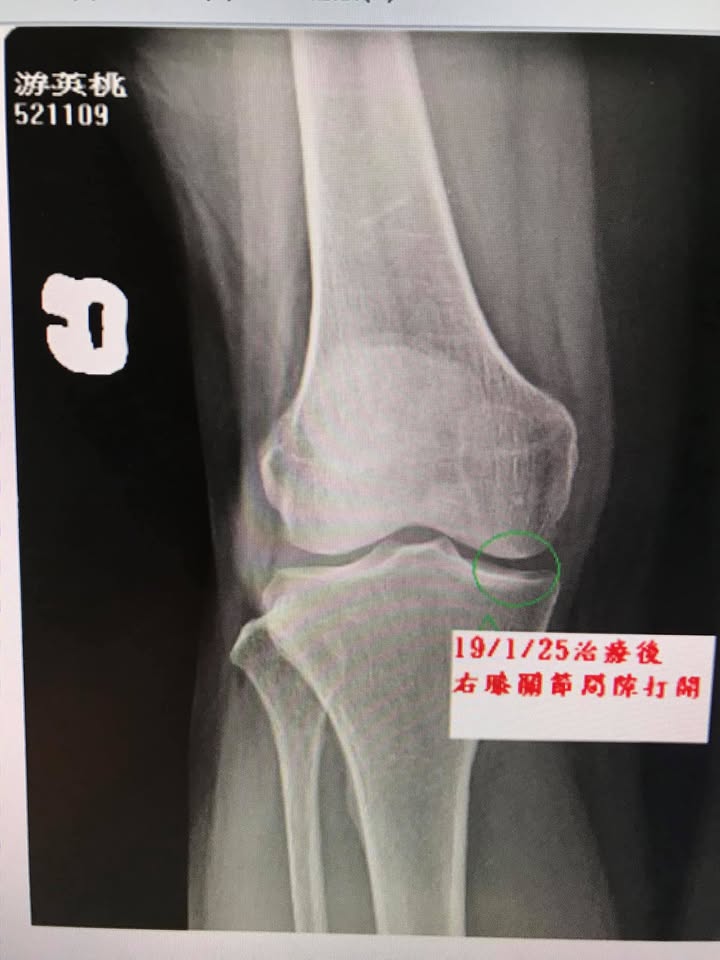

我們非常的開心且訝異,在第二次的治療就感覺膝蓋輕鬆不少,而在八周的治療後,右側膝關節間隙明顯打開,而且原本左側臏骨外翻也改善不少,當然患者臨床症狀大幅度消失,這只是個案報導,並非每個人都有同樣效果,囑咐游大姊還是要常訓練股四頭肌跟避免久蹲久站等會傷害膝關節的動作